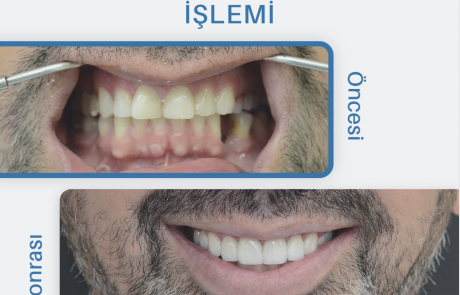

Gülüş Tasarımı

Gülüş tasarımı, bir kişinin dişlerinin şeklini, boyutunu, rengini [...]